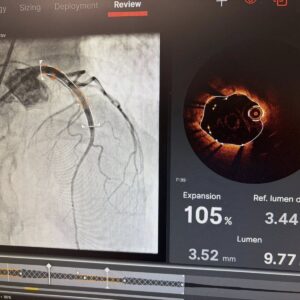

Под ръководството на д-р Александров, екипът на НКБ извърши комбинирана атеректомия под оптичен контрол – процедура, която звучи като сцена от научнофантастичен филм, но е реалност в софийската болница.

Всичко това се случва под безпощадния контрол на Оптичната кохерентна томография (OCT). Това е „златният стандарт“ в диагностиката, който чрез светлинни вълни предоставя на кардиолозите кристално чисто 3D изображение на вътрешността на артерията с микроскопична точност. Благодарение на OCT, лекарите виждат всяка подробност в реално време, гарантирайки перфектното поставяне на стента.